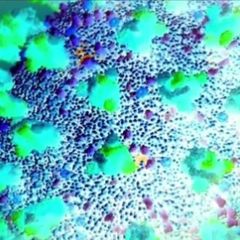

| Colorized scanning electron micrograph of an apoptotic cell (purple) infected with SARS-COV-2 virus particles... |